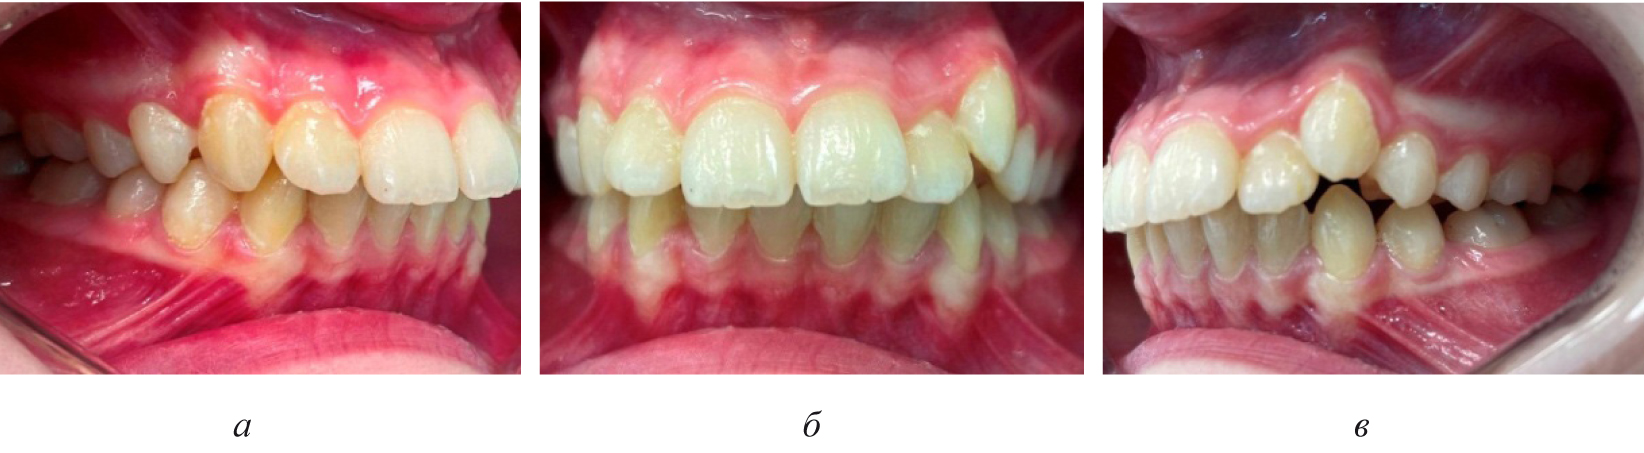

Последующие этапы ортодонтического лечения техникой эджуайс проводились с учетом общепринятого протокола и этапности смены металлических дуг, что способствовало нормализации окклюзионных взаимоотношений (рис. 5).

Рис. 5. Окклюзионные взаимоотношения справа (а), спереди (б) и слева (в) на завершающем этапе лечения

Обращали внимание на расположение центральной точки дуги и ее расположения относительно линии эстетического центра.

Лечение считалось законченным после полной нормализации основных параметров зубных дуг и завершения ретенционного периода.